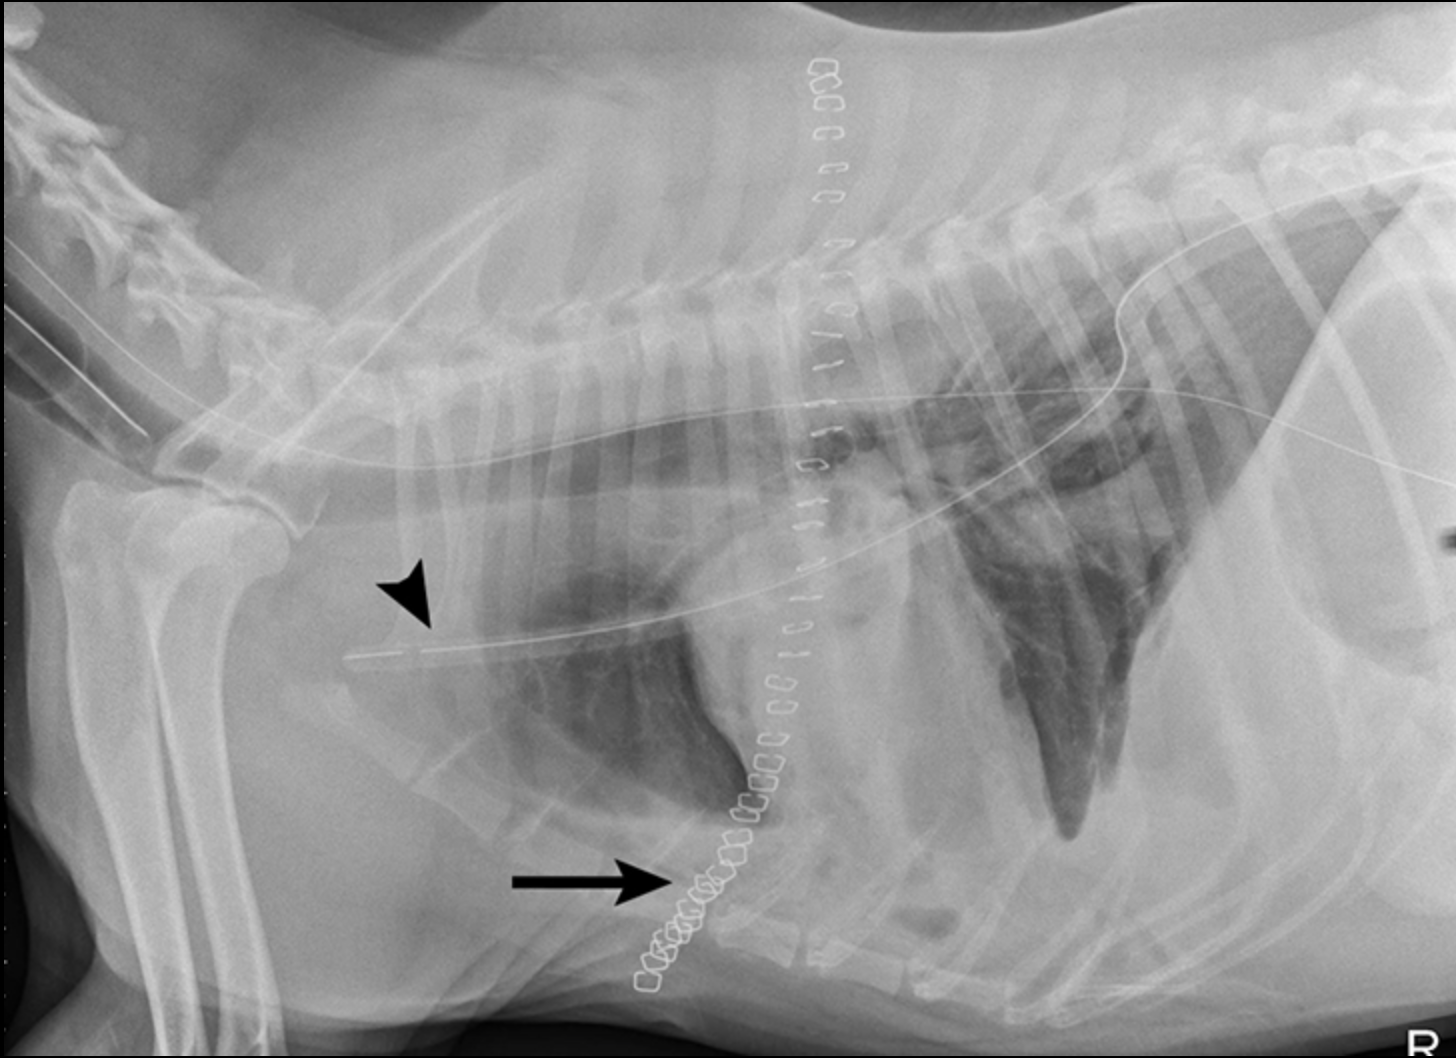

Las radiografías torácicas laterales derechas revelaron una gran cantidad de opacidad de líquido / tejido blando que oscurece la silueta cardíaca. Las radiografías ventrodorsales mostraron un aumento de la opacidad de los tejidos blandos en el hemitórax izquierdo, principalmente en los campos del pulmón craneal y medio. En el hemitórax izquierdo se observó un patrón intersticial leve, una línea de fisura pleural y borramiento del borde en el corazón (Figura 1).

Los hallazgos radiográficos sugirieron una combinación de enfermedad pulmonar y del espacio pleural. Los diagnósticos diferenciales incluyeron derrame pleural (p. Ej., Hemotórax, piotórax, quilotórax, hidrotórax, neoplasia) y la masa del espacio pleural o efecto de masa (p. Ej., Neoplasia, consolidación o torsión del lóbulo pulmonar, absceso / granuloma).